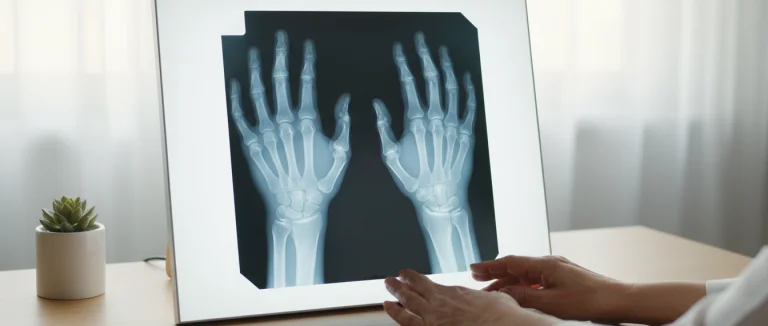

Для подтверждения диагноза применяются несколько методов обследования:

| Рентгенография | Изменения хряща, остеофиты, сужение суставного пространства | Доступность, низкая стоимость |

Важно отметить, что диагностика должна проводиться под руководством специалистов, чтобы исключить другие причины боли в руках, такие как ревматоидный артрит или туннельный синдром.

Симптомы обычно развиваются постепенно. Боль усиливается при движении или нагрузке, часто ощущается в суставах пальцев и запястья. Утром может наблюдаться скованность, длительностью до 30 минут. Появляются отёк и ощущение тепла в поражённом суставе. Снижается сила захвата, затрудняется мелкая моторика. На поздних стадиях могут образовываться узлы‑остеофиты, известные как «шариковый» артроз, видимые на рентгене.

Для подтверждения диагноза врач проводит подробный осмотр и собирает анамнез. Рентгенография показывает изменения хряща, остеофиты и сужение суставного пространства. УЗИ позволяет оценить отёк синовиальной оболочки и наличие кист без ионизирующего излучения. МРТ даёт детальную картину хрящевой ткани и мягких структур, что особенно полезно на ранних стадиях. В редких случаях применяется артроскопия, позволяющая непосредственно осмотреть сустав и при необходимости выполнить лечебные вмешательства.